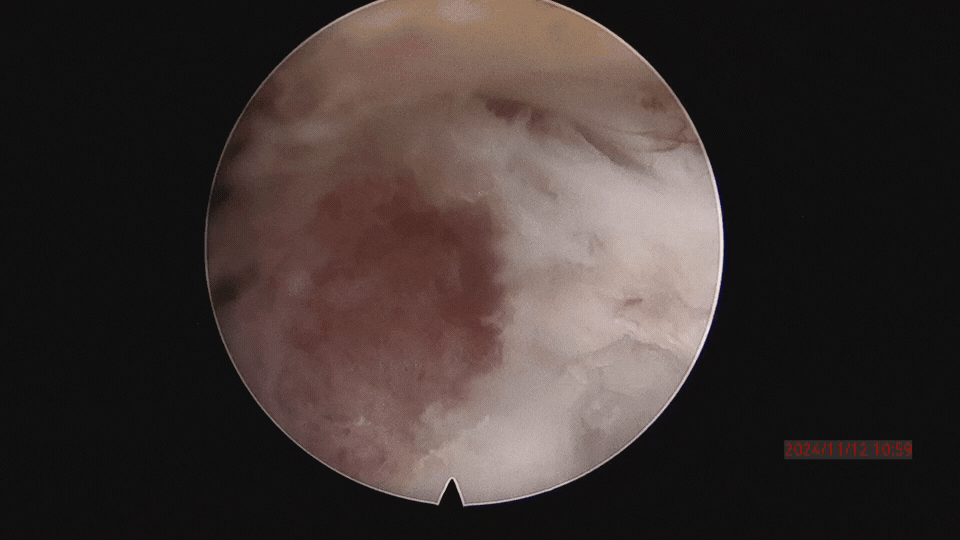

▲取之前,骨块突入椎管、压迫神经。

▲取骨块的过程。